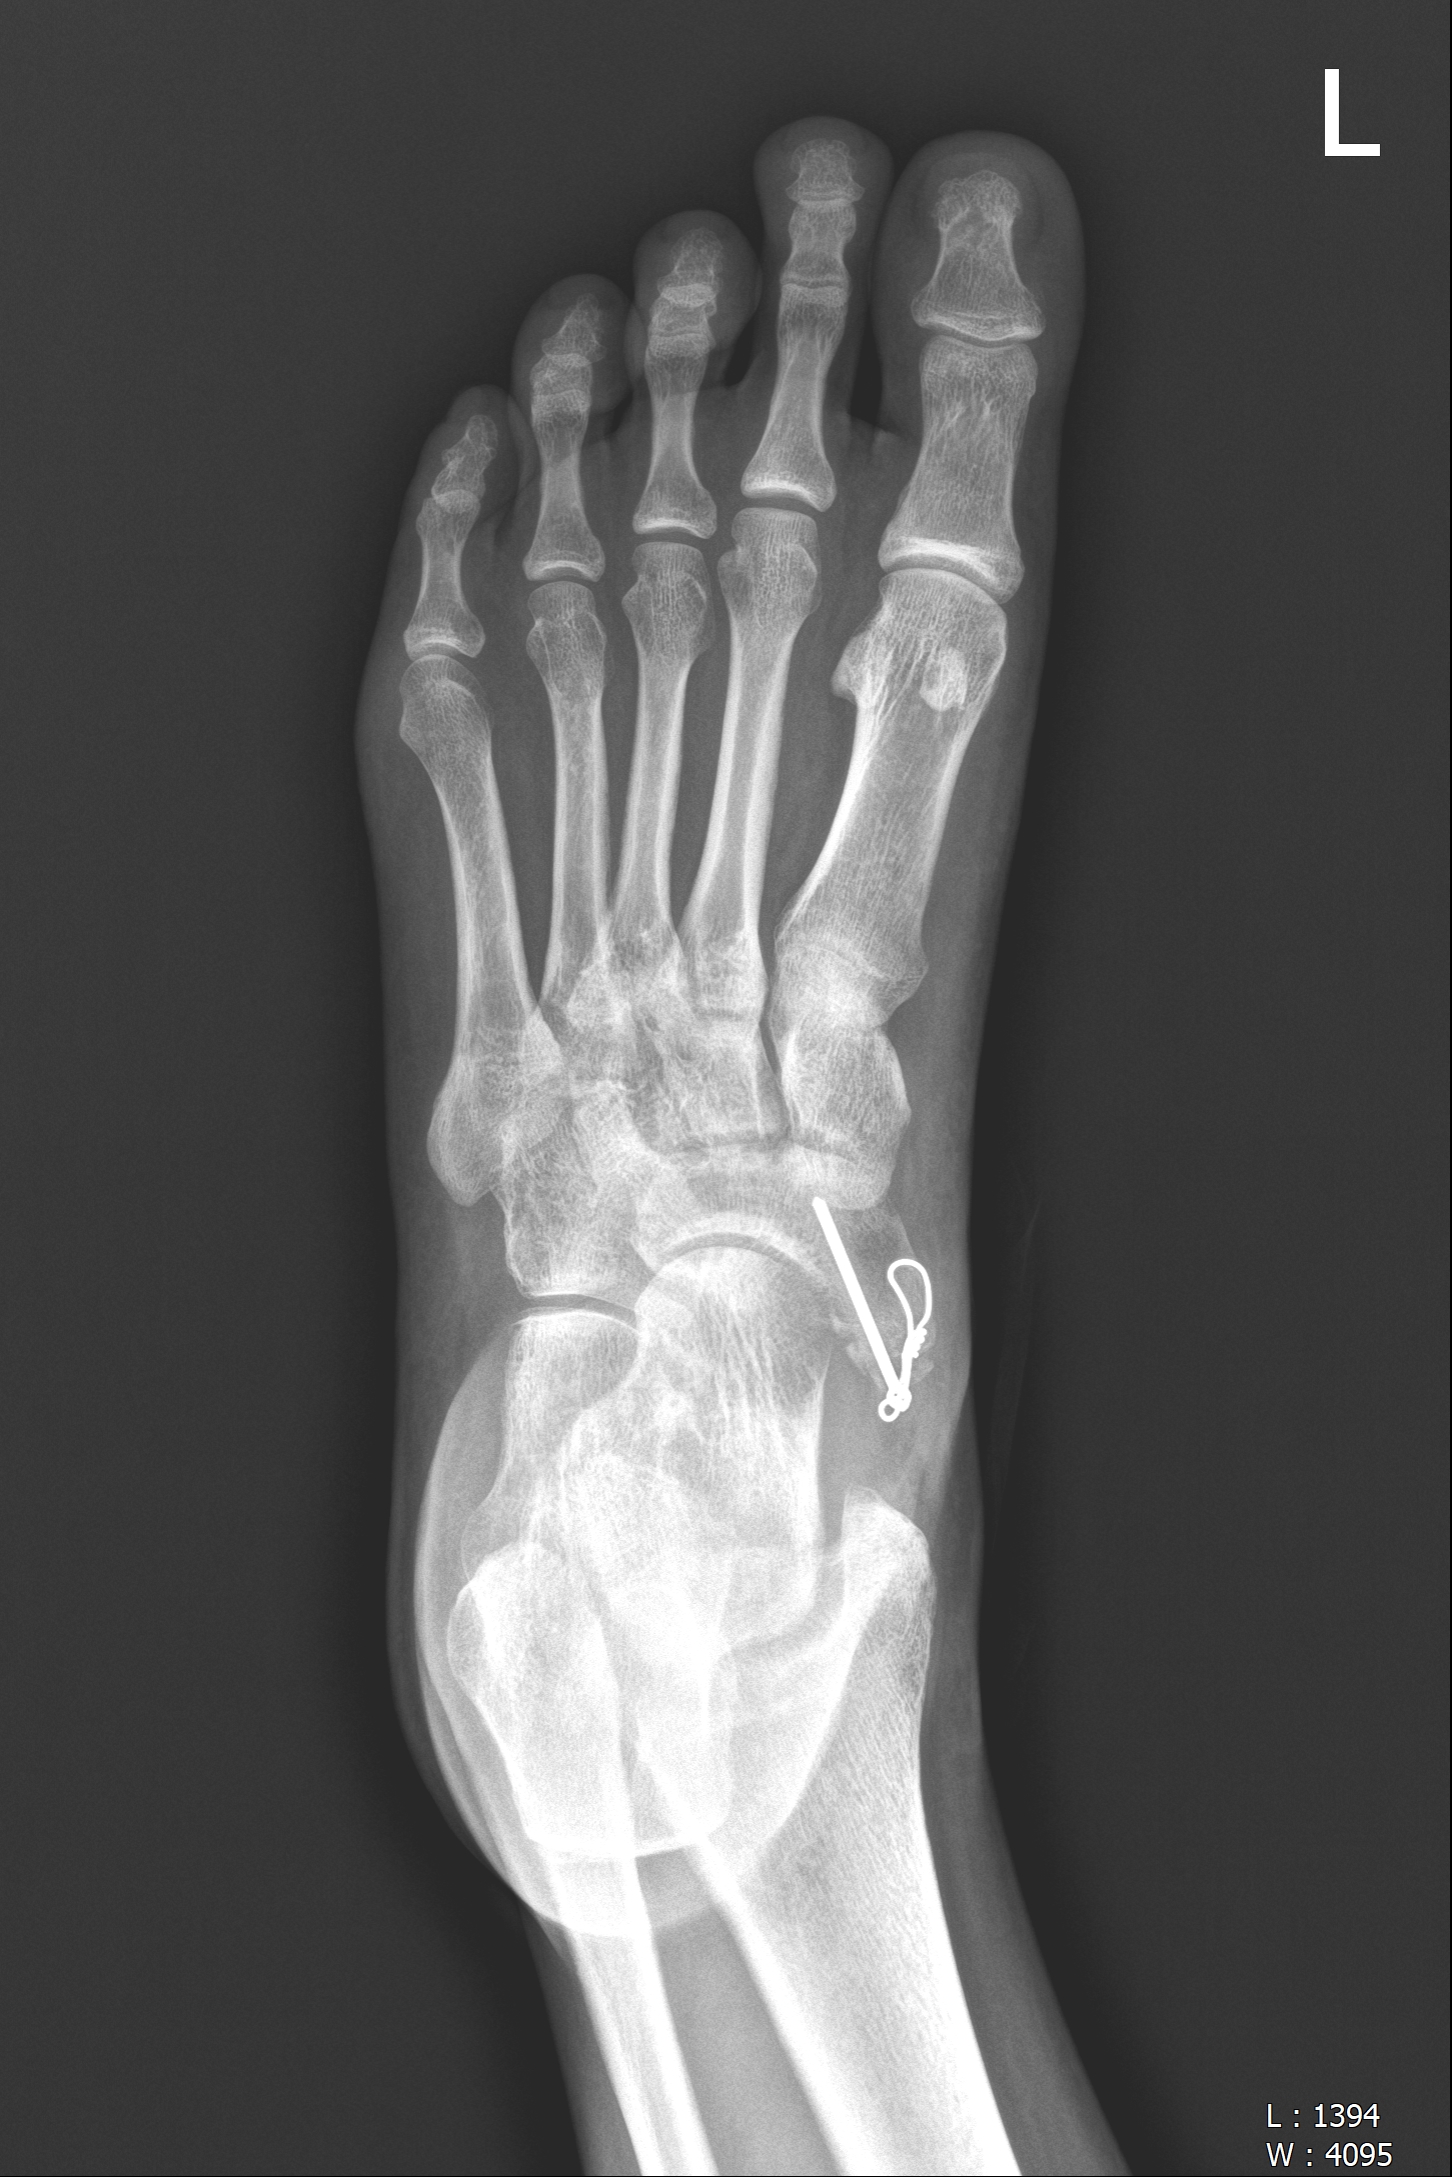

- X-ray, CT : 부주상골 존재여부 및 형상 확인